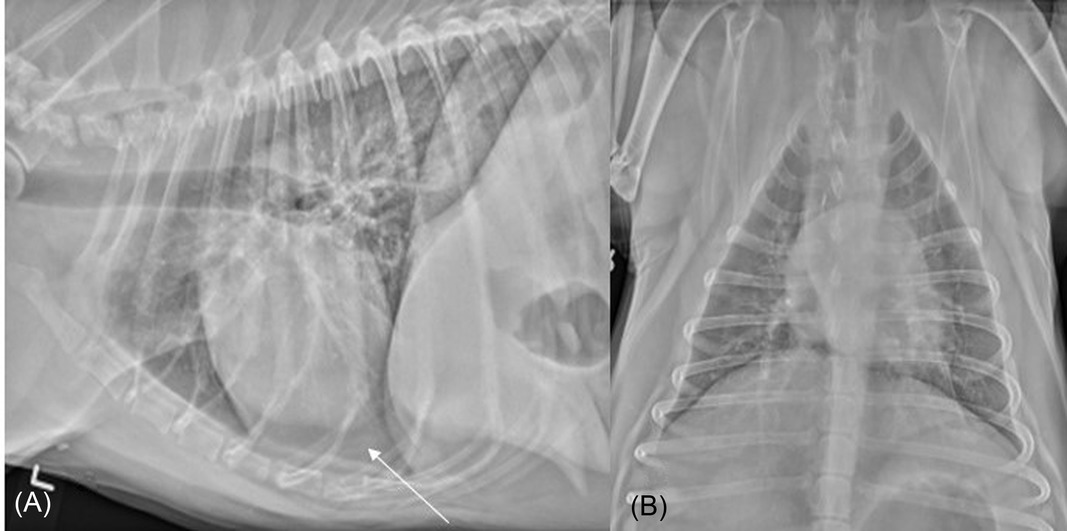

Vetology AI Accurately Detects Pleural Effusion in Canine Thoracic Radiographs

VRU 63(5): 573-579